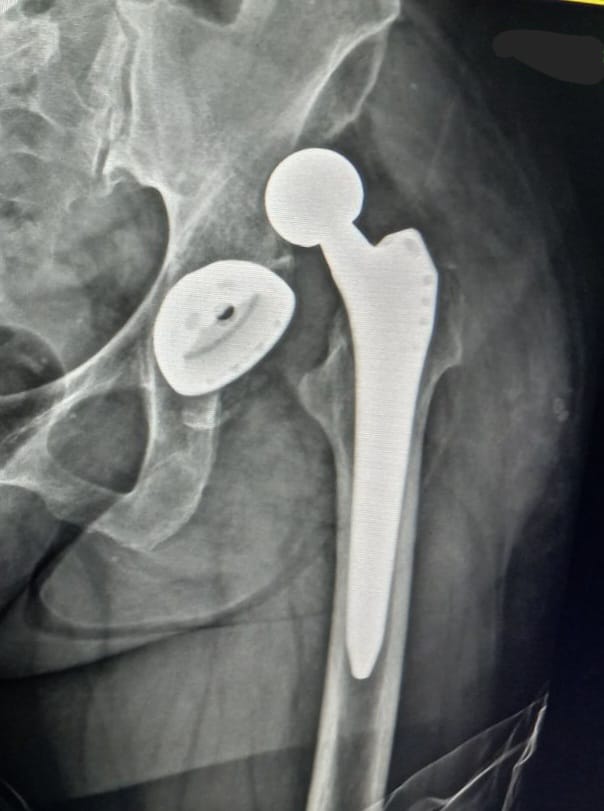

Що не можна робити після ендопротезування

Після ендопротезування важливо знати, що не можна робити, щоб уникнути ускладнень і забезпечити успішне відновлення. Існують певні дії, яких краще уникати, щоб новий штучний суглоб служив довго і без проблем.